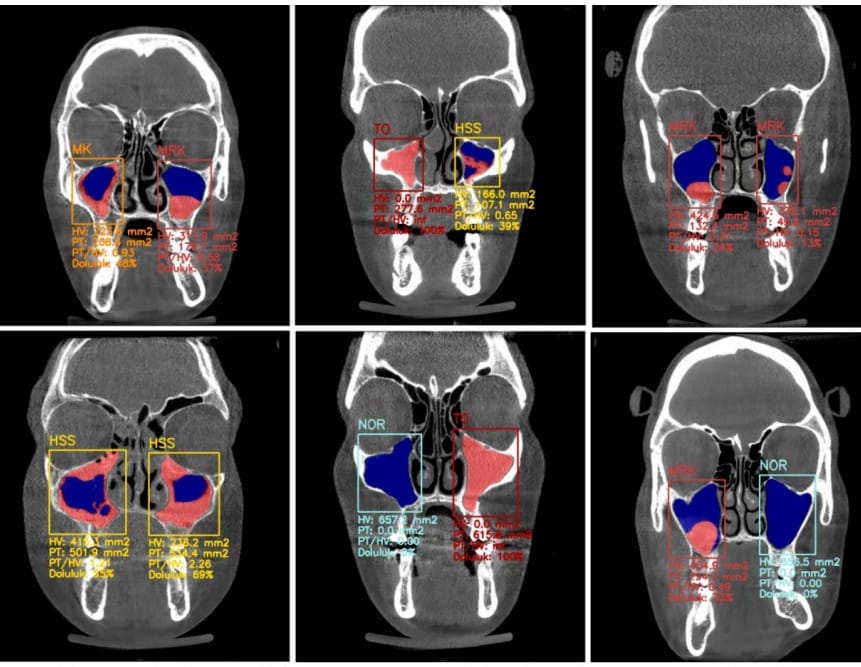

Geleneksel yöntemlerle yapılan teşhislerde insan faktöründen kaynaklanan hataların kaçınılmaz olduğunu ifade eden Taşsöker Bulut, " Yapay zekâ, özü itibarıyla 'veri' ile beslenir. Diş hekimliğinde en somut, en standart ve en zengin veri ise radyolojik görüntülerdir. Diş hekimliğinde teşhise yönelik radyolojik görüntüler üzerinde çalıştığımız için yapay zekâ araştırma yoğunluğu bizim bölümümüzde. 2 boyutlu panoramik filmlerden 3 boyutlu tomografilere kadar çok geniş bir veri havuzuna sahibiz. Yapay zekayı bu sürece dahil etmemizin temel sebebi; insan gözünün yorgunluk, dikkat dağınıklığı veya düşük görüntü kalitesi nedeniyle atlayabileceği milimetrik detayları yakalamaktır. Elde ettiğimiz veriler, yapay zekanın yüzde 99’a varan doğruluk oranlarıyla teşhis yapabildiğini gösteriyor. Bu, neredeyse 'sıfır hata' diyebileceğimiz bir seviye" sözleriyle teknolojinin ulaştığı noktayı özetledi.

Prof. Dr. Melek Taşsöker Bulut, diş hekimliği içinde radyolojinin önemine ve bu alanın toplum, hatta bazen tıp camiası tarafından bile yeterince tanınmadığına dikkat çekti. 5 yıllık temel diş hekimliği eğitiminin ardından 3 yıllık zorlu bir uzmanlık süreci gerektiren bu branşın, çeneler, dişler ve orta yüz bölgesindeki patolojilerin tespitinde kritik rol oynadığını belirten Taşsöker Bulut, Türkiye’de uzman sayısı oldukça az olan bu branşın, iki ve üç boyutlu görüntüleme yöntemlerini (tomografi, panoramik radyografi, MR, ultrason) kullanarak en karmaşık vakaları çözdüğünü vurguladı. Prof. Dr. Taşsöker Bulut, "Normal bir diş hekiminin radyoloji bilgisi, uzmanlık gerektiren teşhis yetenekleri noktasında sınırlı kalabiliyor. İşte yapay zekâ burada devreye giriyor. Bir uzmanın binlerce hasta gördükten sonra edindiği tecrübeyi, bir klinik asistana ya da standart bir diş hekimine aktarabilecek bir köprü kuruyoruz" dedi.

Özellikle nadir görülen hastalıklar, tükürük bezi rahatsızlıkları, karmaşık çene eklemi vakaları ve sinüs patolojileri gibi uzmanlık gerektiren durumlarda yapay zekanın sunduğu analiz yeteneği, yanlış tedavi süreçlerinin de önüne geçecek nitelikte. Taşsöker Bulut, "Hata payını yüzde 1’e indirmek demek, yanlış teşhis nedeniyle kaybedilen zamanın ve sağlığın geri kazanılması demektir" diyerek konunun hayati önemini vurguladı.